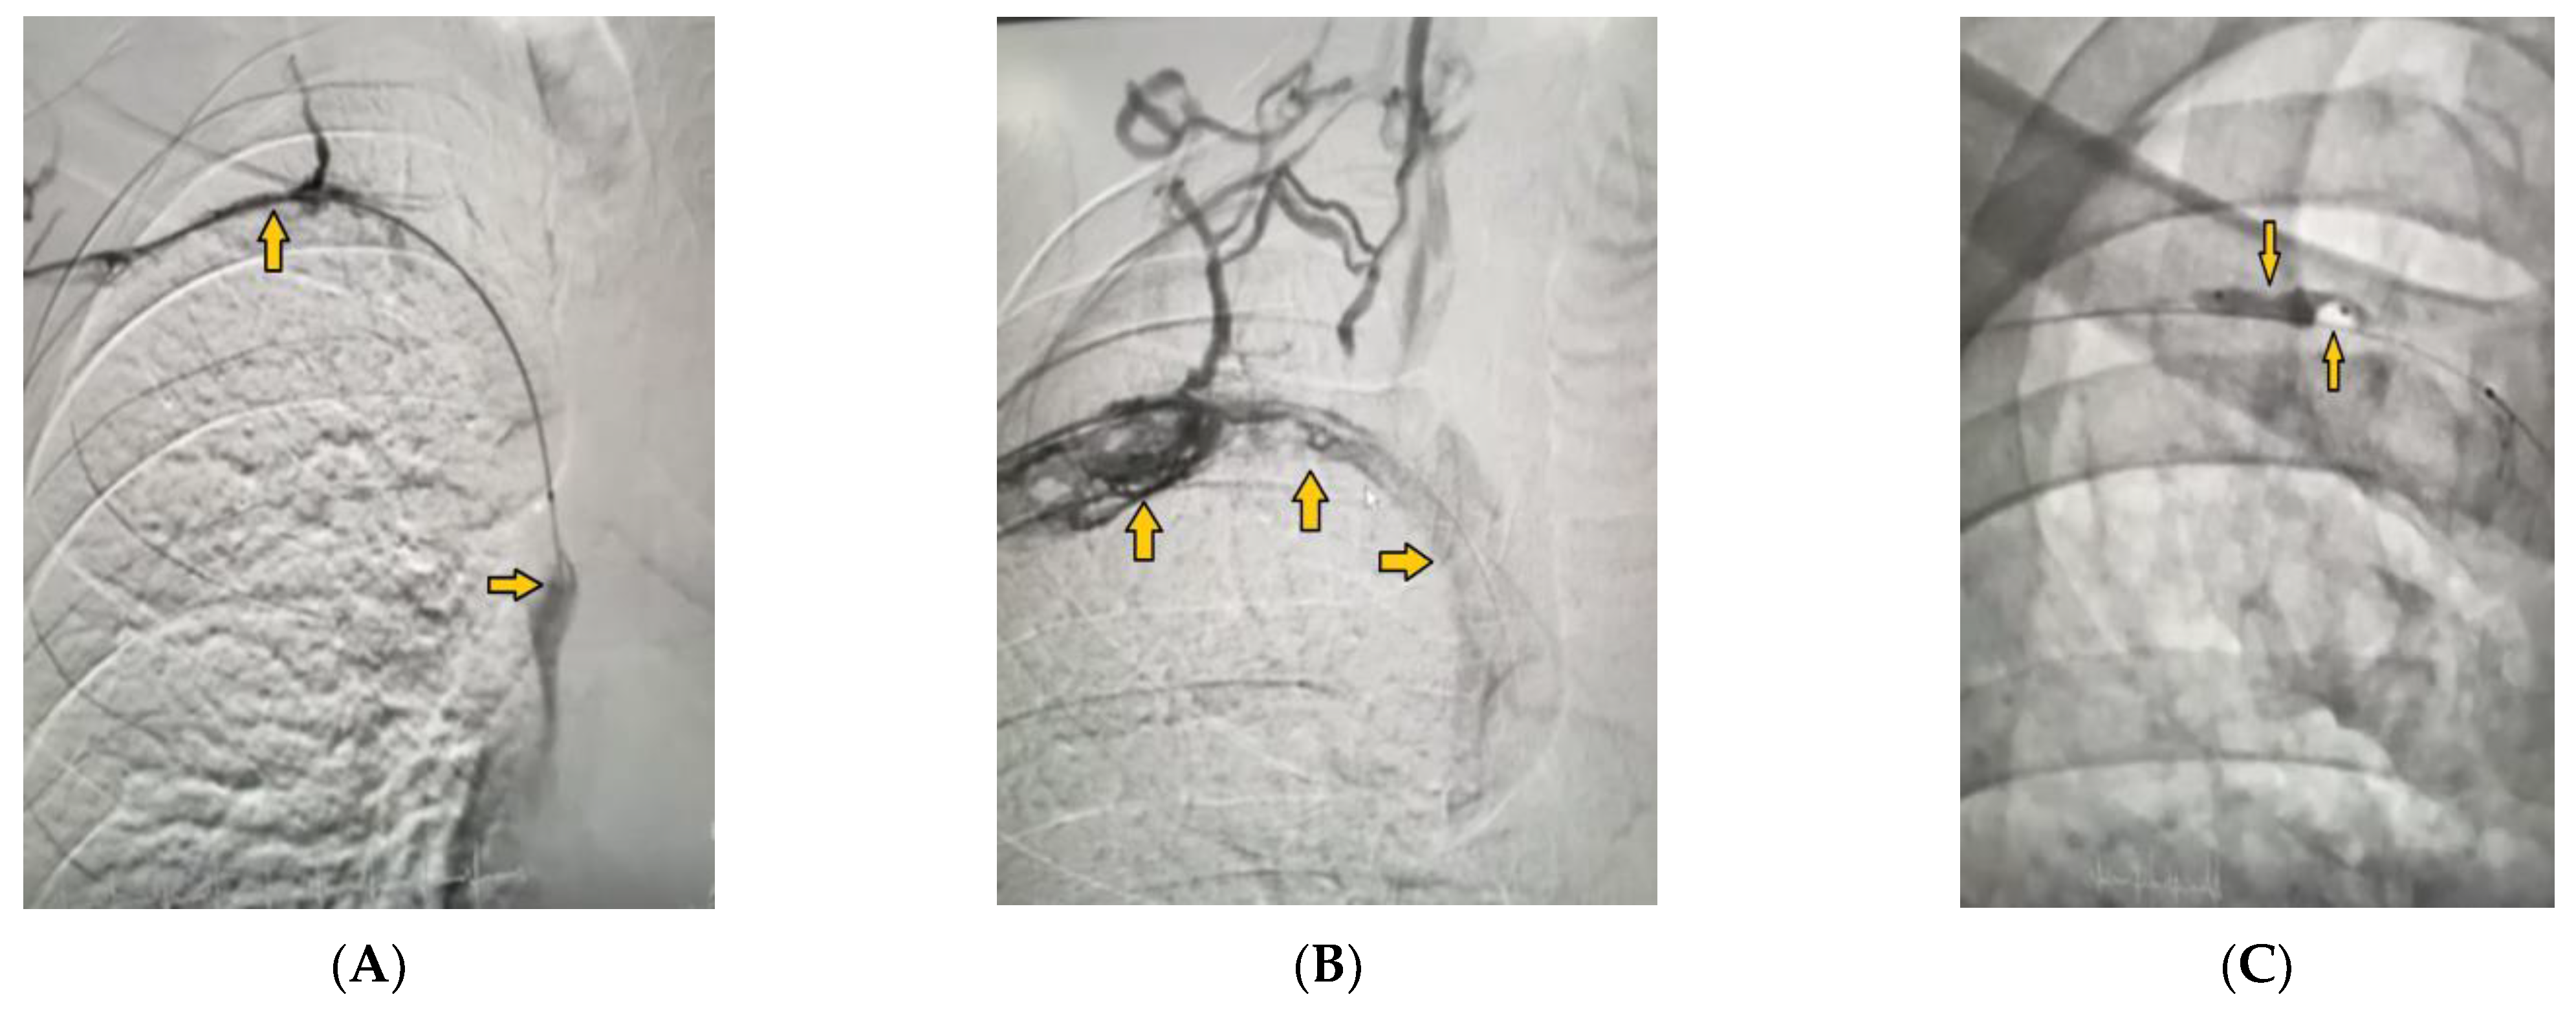

2. Case Presentation